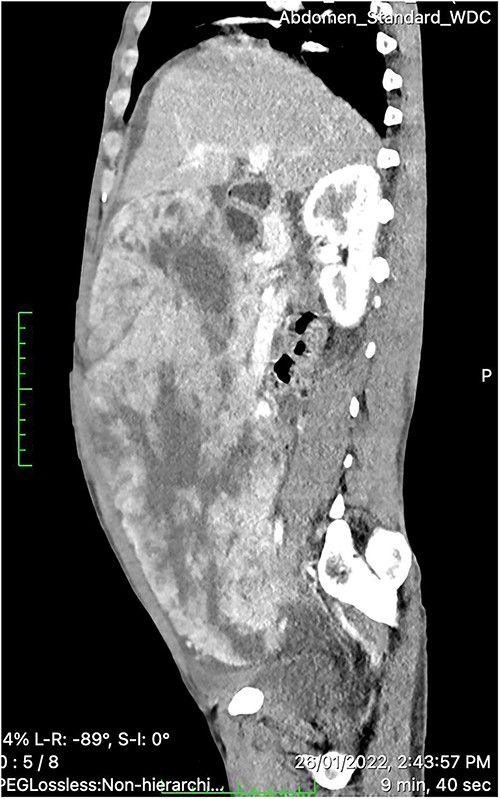

On physical examination, the patient was sick looking but had stable vital signs. Pertinent positive findings were pale conjunctivae, and a huge ill-defined abdominal mass occupying a major portion of the abdominal cavity that was firm to palpation and mildly tender. A routine blood test revealed the hemoglobin of 7.2 gm/dl and a negative fecal occult blood test. Contrast-enhanced CT of the abdomen showed a huge (30 × 26.5 × 15 cm) lobulated heterogeneous hyper-vascular mass lesion filling the whole abdominal cavity and extending down to the pelvis with internal poorly enhancing cystic components (Fig. 1). The tumor appeared to arise from the inferior wall of the gastric wall, and there was no evidence of lymphadenopathy or distant metastases. These findings were consistent with GIST arising from the stomach.

Contrast-enhanced CT scan showing a huge (30 × 26.5 × 15 cm) lobulated heterogeneously hyper-vascular mass lesion filling the whole abdominal cavity and extending down to the pelvis with internal cystic components.